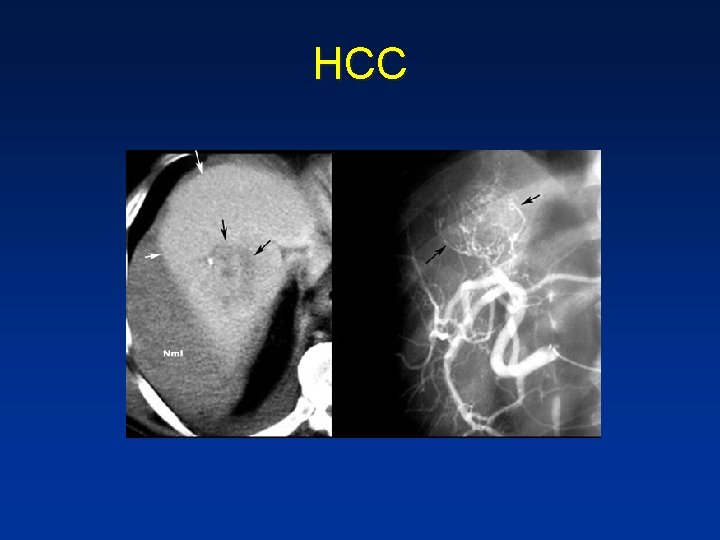

Hepatocellular carcinoma HCC

• Any hypervascular lesion in a cirrhotic liver is hepatocellular carcinoma untill proven otherwise. • HCC may be solitary, multifocal or diffusely infiltrating. • Large HCC typically have a mosaic appearance due to hemorrhage & fibrosis.

• HCC is a silent tumor, so if patients don’t have cirrhosis or hepatitis C , you will discover them in a late stage. • They tend to be large with mozaic pattern , a capsule , hemorrhage and necrosis. • HCC become isodense or hypodense to liver in the portal venous phase due to fast wash-out • On delayed images, the capsule and sometimes septa demonstrate prolonged enhancement.

• Large HCC with mozaic pattern in a non cirrhotic liver

• Cirrhotic liver with hypervascular , inhomogenous lesion. • The inhomogenous enhancement and partial capsule are helpful for the diagnosis of HCC

• Small HCC in cirrhotic liver not visible on NECT , clearly visible on arterial phase, and not visible in portal venous phase

• HCC in cirrhotic liver , notice fast wash out in equilibrium phase compared to surrounding liver parenchyma

HCC

Blood • HCC • Adenoma